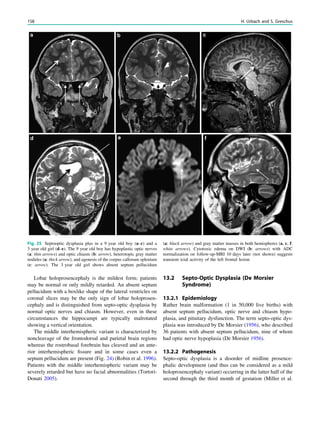

Tuberous sclerosis, 138,145, 165, 167 Type 1 lissencephalies, 132 Type 1, 131 Type 2A, 138 Type 2B, 138 Type I lissencephaly, 131 U Ulegyria, 194, 198, 201 Unprovoked seizure, 26 Urbach–Wiethe syndrome, 174 V Vagus nerve stimulators, 85 Valproate, 252, 253 Varicella zoster, 149 Versive seizures, 11 Vigabatrin, 253 Voltage-gated potassium channels (VGKC), 103 W Wada test, 43, 45, 46 Wake-up seizures, 6 Walker–Warburg syndrome (WWS), 134, 137 West syndrome, 201, 231 Wyburn–Mason syndrome, 185 X X-linked lissencephaly with abnormal genitalia (XLAG), 132 Z Zabramski, 182, 184, 185 270 Index